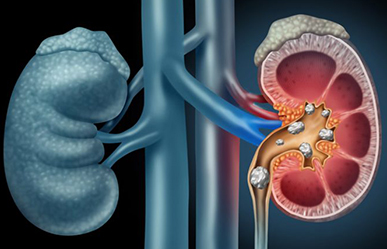

Urologiya və onun nəznində yerləşən Andrologiya bölməsində yüksək ixtisaslı uroloq-androloq həkimlərimizin təcrübəsi ilə birgə qısa müddətdə bütün uroloji...